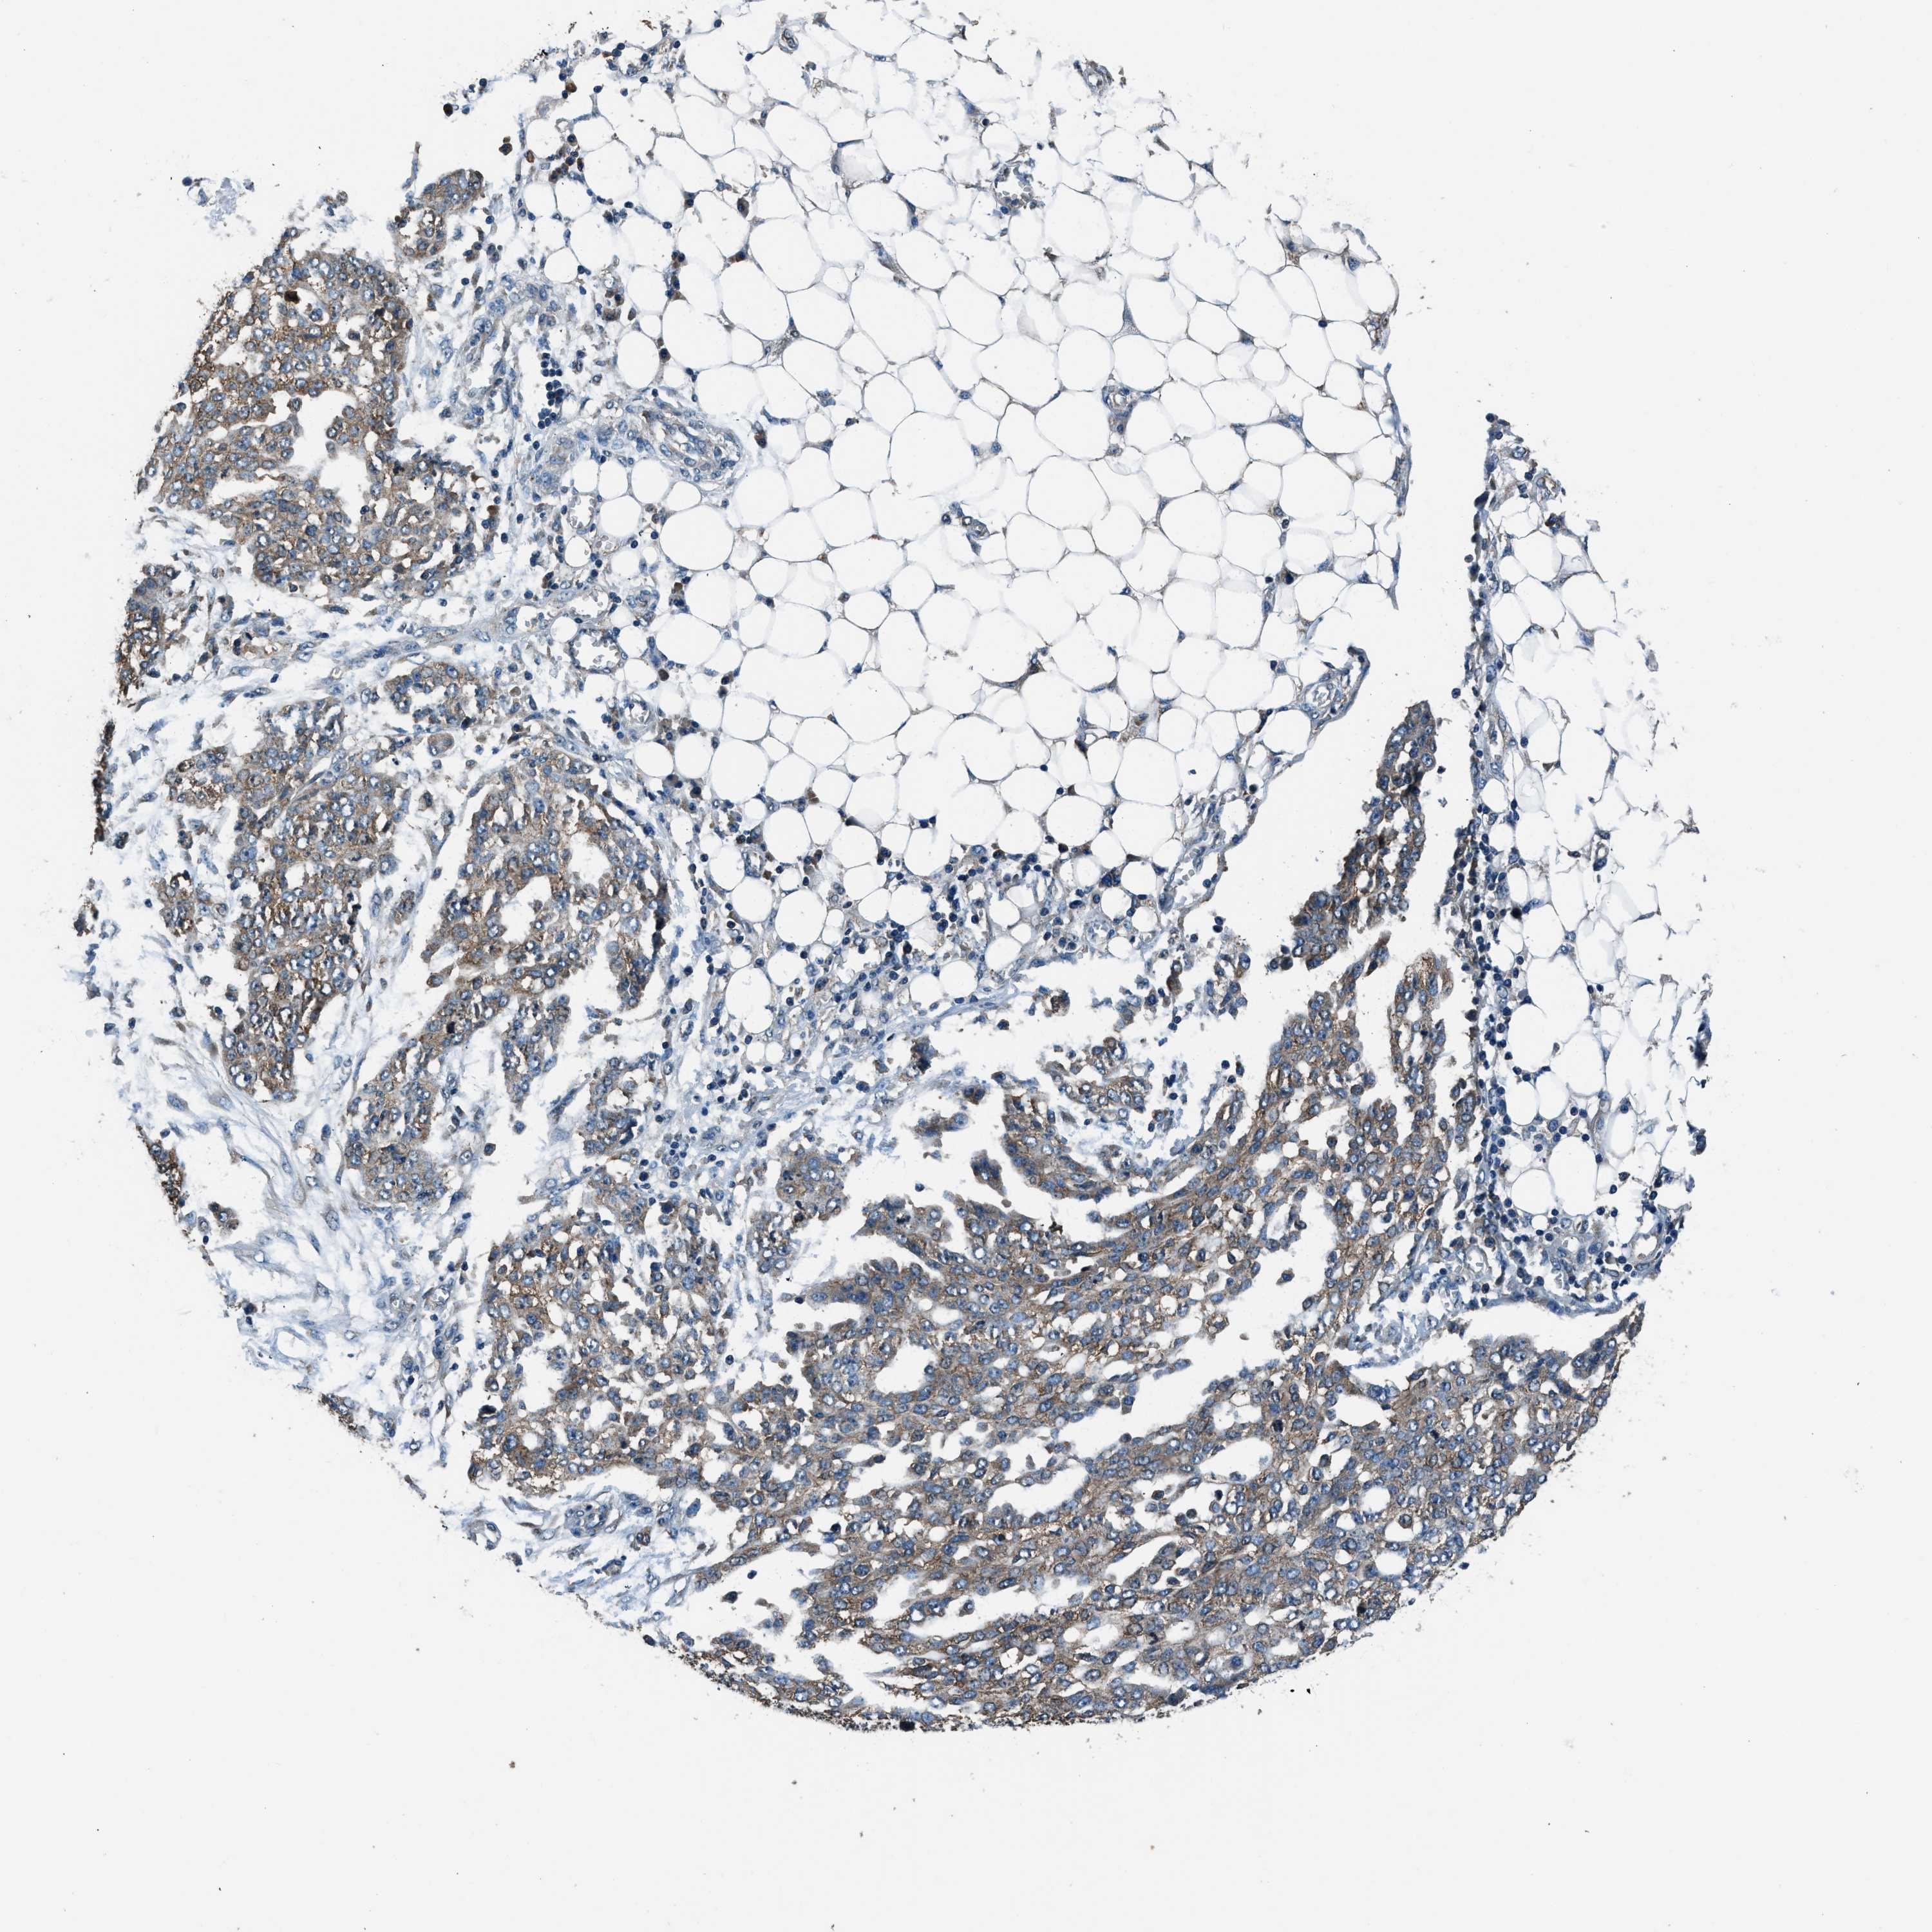

OVARIAN CANCER - Protein expressioni

A mouse-over function shows sample information and annotation data. Click on an image to view it in a full screen mode. Samples can be filtered based on level of antibody staining by selecting one or several of the following categories: high, medium, low and not detected. The assay and annotation is described here.

Note that samples used for immunohistochemistry by the Human Protein Atlas do not correspond to samples in the TCGA dataset.

Antibody stainingi

Antibody staining in the annotated cell types in the current human tissue is reported as not detected, low, medium, or high, based on conventional immunohistochemistry profiling in selected tissues. This score is based on the combination of the staining intensity and fraction of stained cells.

Each image is clickable and will lead to virtual microscopy that enables deeper exploration of all samples and also displays staining intensity scores, fraction scores and subcellular localization as well as patient and tissue information for each sample.

Antibody HPA016649

Antibody HPA018152

Cystadenocarcinoma, serous, NOS

Carcinoma, endometroid

Cystadenocarcinoma, mucinous, NOS

Carcinoma, NOS